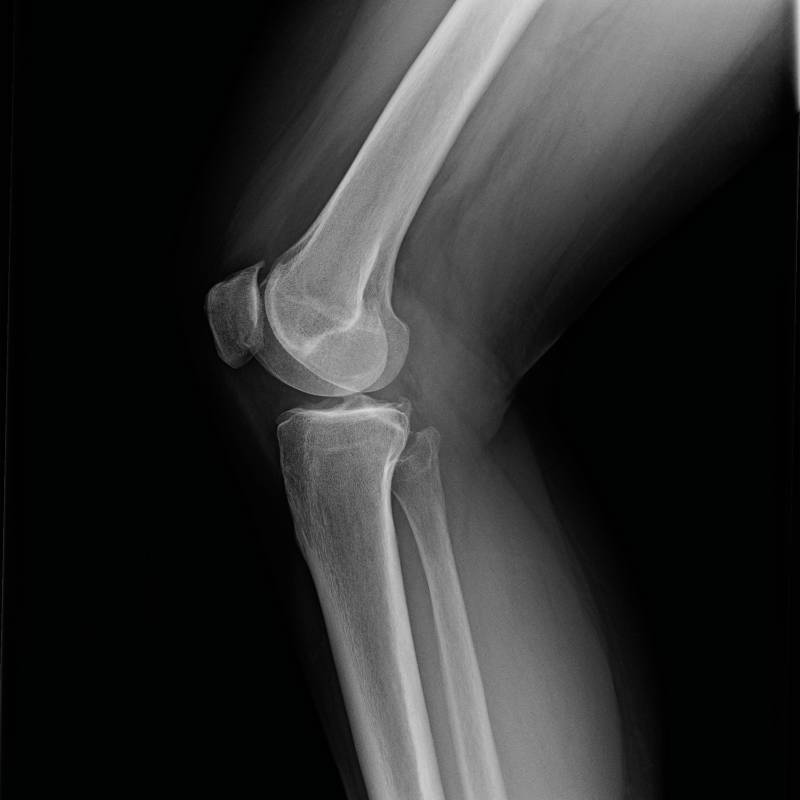

Digunakan untuk mengesan masalah pada sendi lutut.

Pemeriksaan sinar-X pada tulang keting.